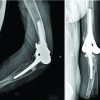

This study reported eight cases of rapidly progressive OA resulting in FHC. Patients initially presented with hip pain and OA, which deteriorated rapidly into severe femoral head failure requiring surgery in as little as 10 weeks (Fig. 1) following an IA corticosteroid with local analgesic injection. Notably, this patient cohort exhibited a range of comorbidities, including obesity, a smoking history, prior cancer treatment, and deficiencies in Vitamin D levels. This convergence of factors underscores the complex interplay between treatment outcomes and individual health circumstances, warranting a comprehensive assessment of risk factors and potential benefits prior to initiating such interventions.

IA corticosteroid therapy has been a longstanding method to alleviate joint inflammation and pain. Its effectiveness in relieving symptoms associated with OA, structural issues, and inflammatory conditions is well-established. Nevertheless, this therapy has raised worries about possible negative impacts on joint cartilage. Research has shown the influence of corticosteroids on the well-being of cartilage, revealing a total decline in the viability of chondrocytes and compromised integrity of the cartilage itself [5]. Notably, in vitro studies revealed complete loss of chondrocyte and synoviocyte viability after a single dose of betamethasone, methylprednisolone, or triamcinolone, potentially leading to cartilage degradation and compromised integrity [6]. These results show fast cell destruction, which may play a role in the integrity of the hip joint. While information is still limited concerning the damaging effects on the cartilage in IA injections for the hip, the chondrotoxicity of local anesthetics utilized in these injections has also been suggested [6-8]. This could potentially lead to cellular demise and structural alterations in the articular cartilage, leading to osteonecrosis and/or collapse of the bone matrix. Research suggests that their application could induce cell death and structural changes in the articular cartilage in a matter of weeks [8]. Recent in vitro research by Mwale et al. in 2023 found that bupivacaine, levobupivacaine, and ropivacaine triggered apoptosis, as indicated by increased caspase-3 activity, within 24 h of induction of the drug [9]. Properly evaluating the balance between short-term pain relief benefits and potential long-term cartilage risks is essential when considering what combination of IA injections to utilize. One patient within the cohort underwent injections in both hips, but a notable distinction emerged in terms of the ensuing outcomes (Fig. 2). Rapid OA leading to FHC manifested unilaterally, presenting an intriguing contrast. The divergent factor lay in the choice of local anesthetic used (Table 2). Both hips received triamcinolone corticosteroid injections in combination with a local anesthetic. Specifically, the right hip received treatment with bupivacaine and exhibited FHC 6 months later (Fig. 2a and b). Conversely, the left hip, treated with lidocaine, showed no indications of FHC (Fig. 2c and d). Studies have shown that both bupivacaine and lidocaine are more chondrotoxic than others [10]. However, Farkas et al. discovered in their in vitro studies that 0.5% bupivacaine was more toxic than 1% lidocaine. Bupivacaine induced almost 100% cell necrosis after 24 h of exposure to human chondrocytes [11]. This leads to the need for caution when determining the type of IA injection to use.